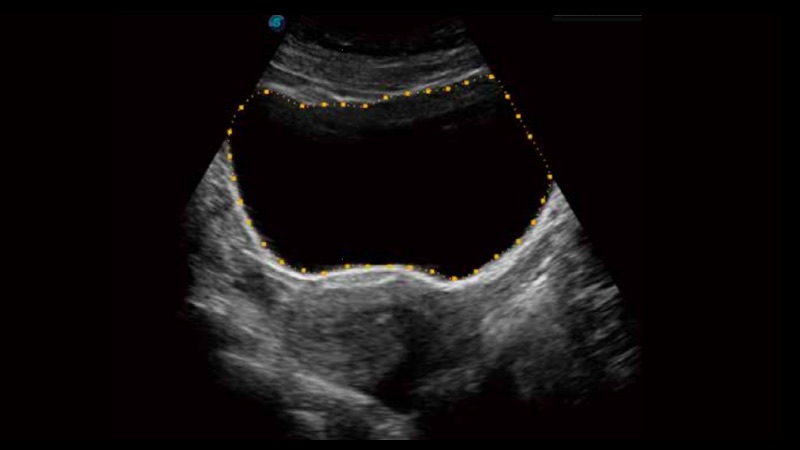

One key bladder wall tracing and volume measurement from Auto Bladder can efficiently provide more accurate contour and results, which is not subject to the bladder shape and size.